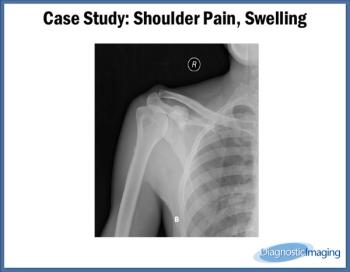

Case History: 24-year-old male with complaints of shoulder pain, slowly increasing swelling for five years.

Published: May 27th 2014 | Updated: